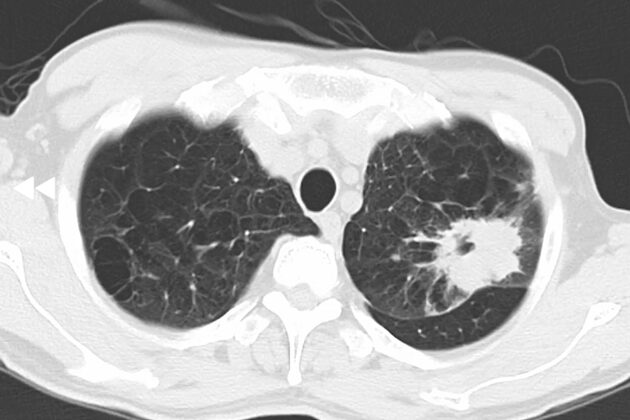

原発巣精査で肺野に空洞性病変

肺気腫所見の中に不整形の腫瘤影。腫瘤辺縁から棘状影(スピキュラ)がみられる。

肺癌脳転移疑い。